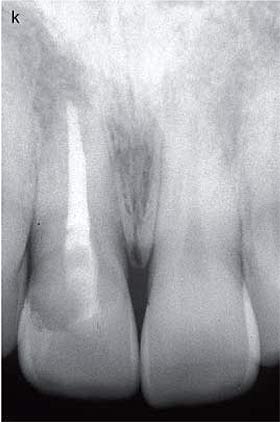

restoration has been refaced because of some surface creasing. (k) A 10-year

follow-up radiograph shows no evidence of further resorption or periradicular

pathology. From (23). Reproduced with

permission from Quintessence Publishing.